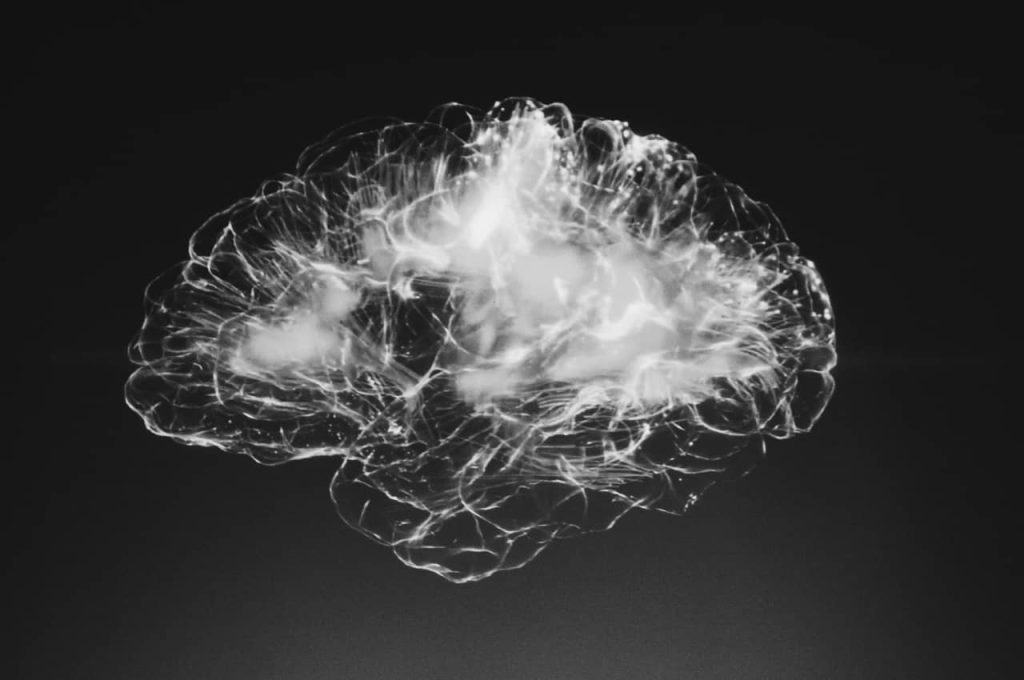

How Long Does It Actually Take to Break an Addiction and Rewrite the Brain?

Addiction not only affects behavior but also physically alters the brain’s structure and function. Many people wonder how long it takes to rewire the brain from addiction, and whether the brain can truly heal. This blog delves into the science of brain rewiring, how long the process takes, and actionable steps for breaking free from addiction and retraining the brain. Support for addiction recovery is available at The Ohana Hawaii, a top-rated residential rehab on the Big Island.

Understanding Addiction and the Brain

Addiction is a complex condition that changes the brain’s wiring, making it difficult to control impulses and behavior. But with treatment and time, it is possible to heal and rewire the brain for healthier habits.

What Happens to the Brain During Addiction?

Addiction hijacks the brain’s reward system by flooding it with dopamine—a neurotransmitter associated with pleasure and reward. Over time, the brain becomes reliant on the substance to release dopamine, making it difficult to experience pleasure from everyday activities. This rewiring of the brain’s reward circuit is what makes breaking an addiction so challenging. Combatting addiction then requires an additional round of ressetting and rewiring the brain’s reward system.

The Science of Brain Rewiring

You may have heard of the concept of “brain retraining” and wondered how it’s possible after addiction has altered the neural circuits in your brain. The answer lies in neuroplasticity—the brain’s remarkable ability to adapt and change throughout life. Structural plasticity refers to the physical changes that occur as the brain rewires itself, forming new neural connections. Studies have shown that as individuals recover from addiction or learn new skills, neurons can extend new connections, or “dendritic branches,” which allows for the creation of new synapses. This rewiring is especially enhanced during significant life changes, such as entering a residential treatment program at The Ohana, where the brain is given the chance to recover in an environment free from habitual cues.

With the right interventions, like therapy, mindfulness practices, and lifestyle adjustments supported by The Ohana’s clinical staff, the brain can heal, enabling individuals to form healthier behaviors and manage cravings more effectively